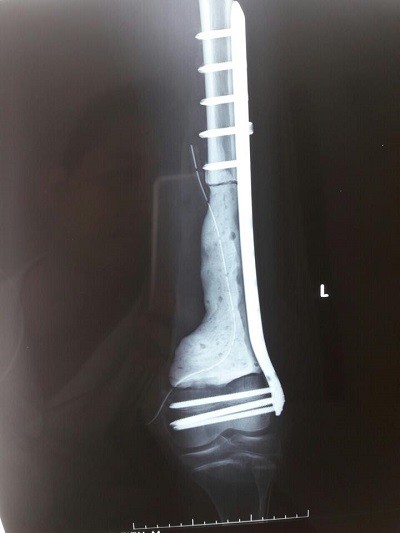

Chia sẻ về ca bệnh PGS. TS. Trần Trung Dũng - Phó Giám đốc Bệnh viện Xanh Pôn, giảng viên trường Đại học Y Hà Nội- người mổ cho bệnh nhi T cho biết: Sau khi hội chẩn, bệnh nhi được tiến hành phẫu thuật, e kip phẫu thuật gồm nhiều chuyên gia của Viện K, Saint Paul và Đại Học Y Hà Nội, sau khi phẫu thuật lấy hết khối u ở đầu dưới xuong đùi, gần khớp gối cho bệnh nhi T.

Và sẽ được duy trì khoảng trống bằng xi măng sinh học và cố định bằng nẹp vít xương đùi. Sinh thiết tức thì trong mổ các diện cắt xương và phần mềm không còn tế bào ung thư. Bảo tồn được chức năng khớp gối và thẩm mỹ cho bệnh nhân.

Dự kiến điều trị hoá chất theo phác đồ tiếp tục. Đánh giá lại sau 3-6 tháng để quyết định ghép xương.